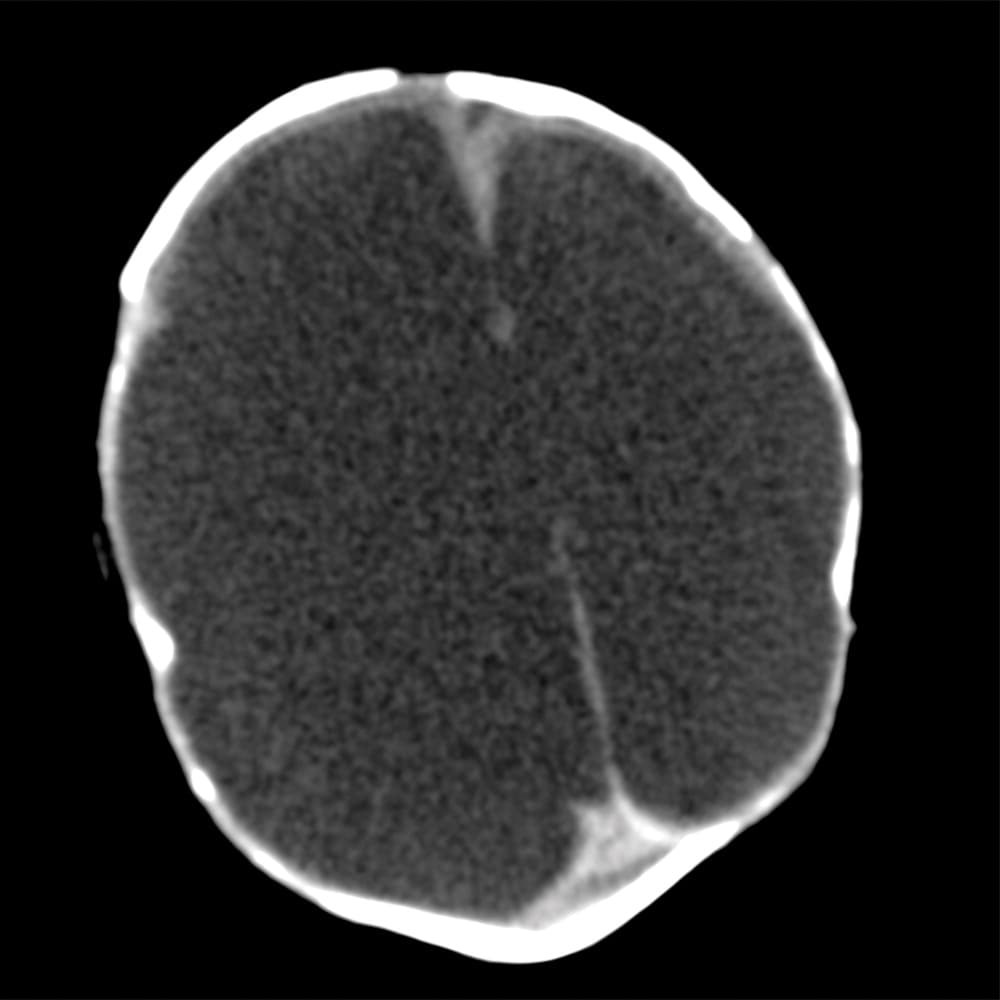

Investigadores brasileños difundieron este martes el mayor número hasta ahora disponible de imágenes computarizadas, resonancias magnéticas y ultrasonidos, de bebés y fetos infectados con el virus del Zika. El daño es mucho mayor del que anticipaban.

Así describe la radióloga brasileña Fernanda Tovar-Moll lo que vio al analizar centenares de imágenes computarizadas, resonancias magnéticas y ultrasonidos de 45 bebés que se contagiaron de zika en el vientre materno en el estado de Paraíba, en el noreste del país, donde el brote ha sido severo.

La mayoría nació con microcefalia, cuya característica más llamativa es que tienen el cerebro y la cabeza más pequeña. Pero muchos sufren una escala y severidad de daño mucho peor en partes importantes del cerebro como el cuerpo calloso, que conecta los dos hemisferios; el cerebelo, que juega un papel significativo en el movimiento, equilibrio y habla; y los ganglios basales, que controlan el pensamiento y la emoción.

Tovar-Moll es coautora de un estudio publicado el martes en la revista Radiology y fue liderado por la doctora Patricia Soares de Oliveira-Szejnfeld, a quien se le da crédito por establecer el vínculo entre el zika y la microcefalia en Brasil.